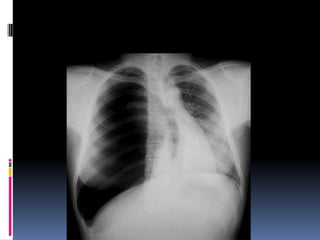

Lung fields

   Infiltrates

   Increased interstitial markings

   Masses

   Absence of normal margins

   Air bronchograms

   Increased vascularity

Cannon ball appearance- DDS

Osteogenic sarcoma

Thyroid (follicular)

Testicular carcinoma

Kidney

Choriocarcinoma

Prostate

Malignant melanoma,       Some GI,    Some very

advanced      nasopharyngeal, and    pharyngeal

carcinomas

Breast

Lymphangitis carcinomatosa

Lung fields  Infiltrates  Increased interstitial markings  Masses  Absence of normal margins  Air bronchograms  Increased vascularity

Cannon ball appearance-DDS Osteogenic sarcoma Thyroid (follicular) Testicular carcinoma Kidney Choriocarcinoma Prostate Malignant melanoma, Some GI, Some very advanced nasopharyngeal, and pharyngeal carcinomas Breast Lymphangitis carcinomatosa